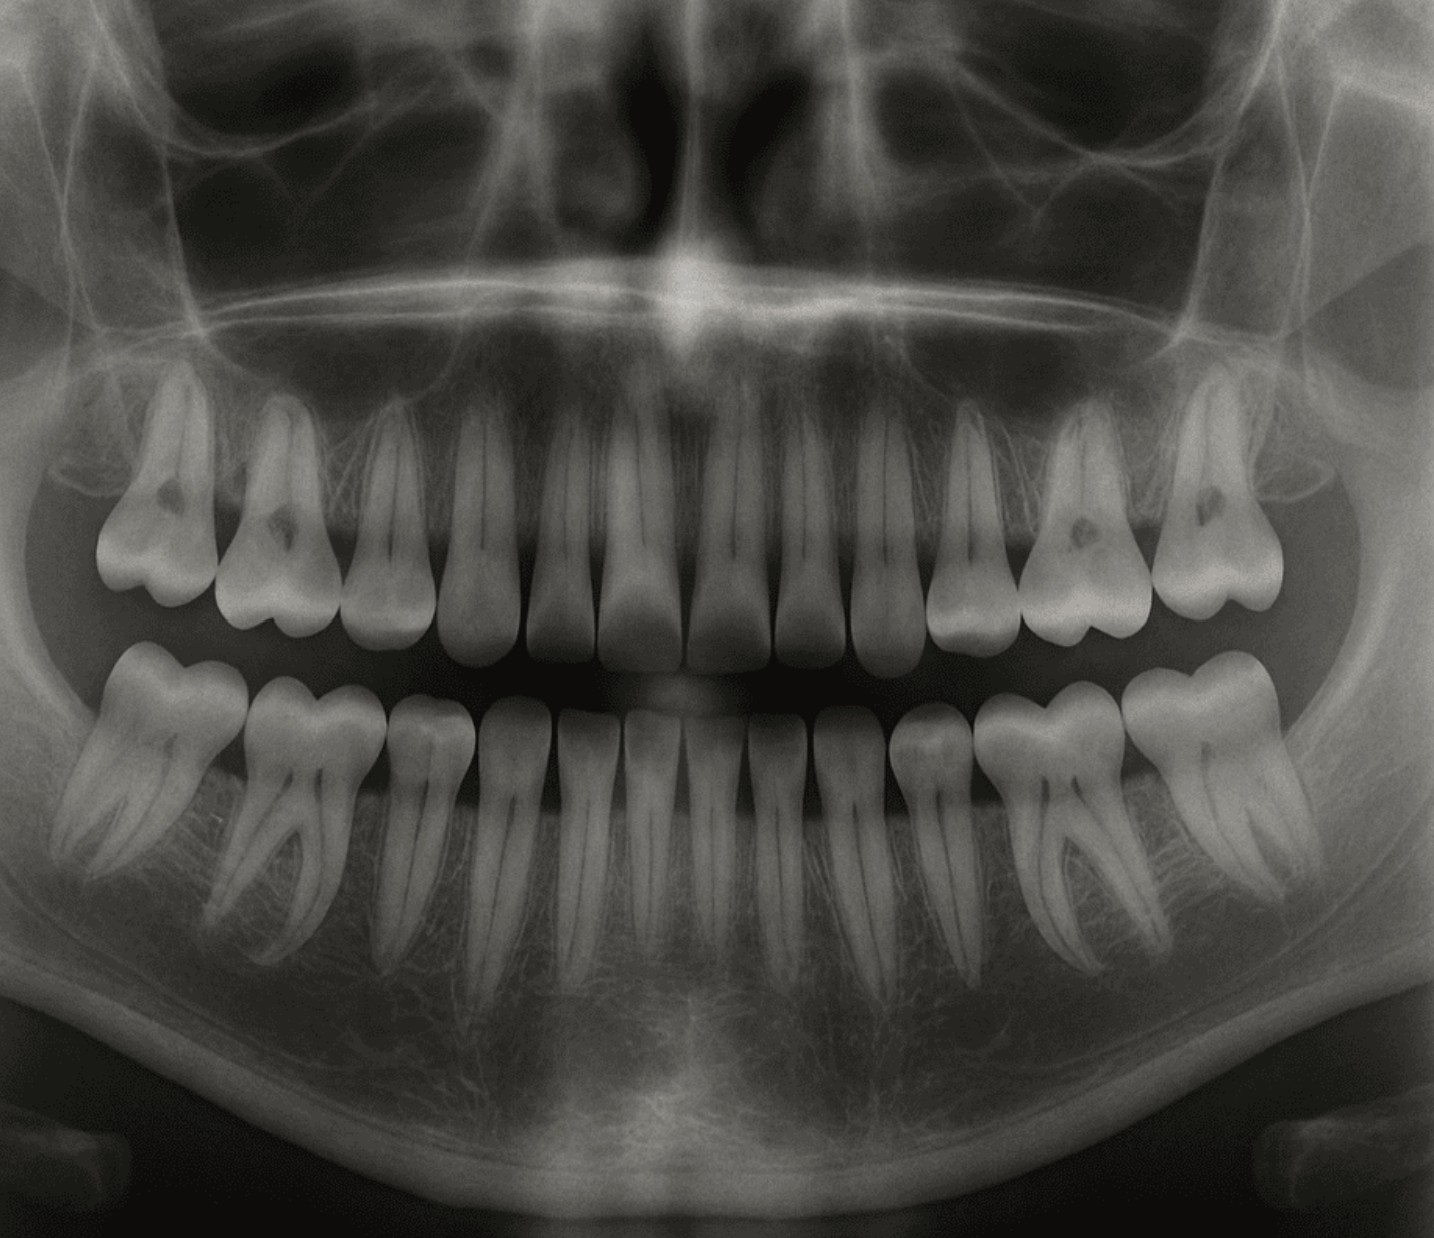

報道によると、日本の京都大学を中心とする研究グループは、歯の成長を抑制する「USAG-1」というタンパク質を阻害する抗体を利用し、再び歯の芽を活性化させて成長させる方法を発見したとのことです。

現在、2024年10月から京都大学で第1段階の臨床試験が行われており、2030年の実用化を目標に開発が進められています。

研究者らは、この薬が永久歯を失った人や、先天的に歯が欠けている人の新たな治療法につながる可能性があると述べています。